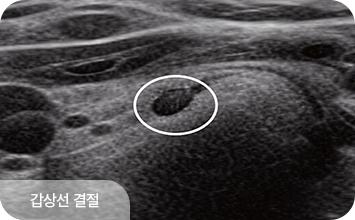

갑상선은 평소에는 잘 만져지지 않지만, 이상이 생겨 커지면 목에서 혹처럼 만져질 수 있습니다.

갑상선에 생긴 혹을 갑상선결절이라 하며, 이 중 악성이 바로 갑상선암입니다.

갑상선 결절의 악성 여부를 판단하는 데 가장 흔히 시행되는 방법으로,

갑상선 세침검사는 아주 가는 바늘을 사용해 갑상선 결절에서

세포를 소량 흡인한 뒤 현미경으로 세포의 모양을 분석하여

양성인지 악성 가능성이 있는지 확인하는 검사입니다.

갑상선 질환은 결절의 크기보다,

구조적 특성과 변화 양상을 함께 살펴야 합니다.